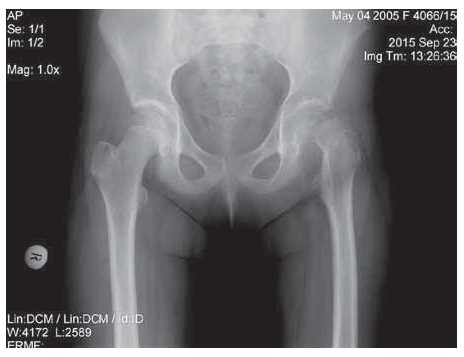

Patient M., 10 years old, was transferred from the Central District Hospital of the city of T. with the diagnosis of closed subcapital fracture of the left femur neck with the displacement of the fragments. His medical history indicated that the trauma had occurred 5 days earlier following a fall from height. The patient was conservatively treated, the left lower limb was immobilized with a derotation plaster cast, and symptomatic therapy aimed at arresting the pain syndrome was performed. Analysis of the radiography of the hip joints in frontal projection (Figure 3) confirmed a type Ia fracture according to the Colonna classification, external-rotational position of the left femur, and downward and posterior epiphysis displacement.

Fig. 3. Patient M. before treatment: radiograph of the hip joints before the operation in a direct projection: total disruption of the integrity of the neck of the left femur in the subcapital zone with the displacement of fragments